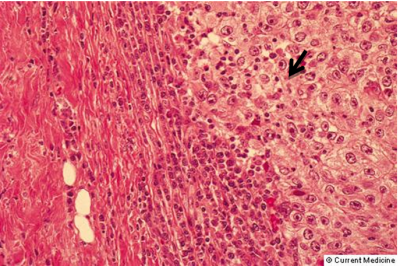

הסיווג הפתולוגי (Grade)

רוב השאתות הממאירות בשד מקורם בצינורות החלב ולכן הן נקראות (75%) Ductal carcinoma. מקור אחר לנגעים ממאירים בשד הן בועיות החלב הנקראות Lobular carcinoma (כ-20%-15%). שאר הנגעים מקורם ברקמת החיבור של השד וברקמה הלימפתית (סרקומות, לימפומות, לויקמיות ועוד). חלק ניכר מהשאתות האפיתליאליות בשד מתפתחות ב-Terminal ductal lobular unit (TDLU) (איור 18.12). צינוריות ובועיות החלב מכוסות באפיתל קובואידלי חד שכבתי היושב על ממברנה בזלית. בין הממברנה הבזלית לתאי האפיתל, נמצא את התאים המיואפיתליאלים המכווצים את צינורית החלב ובועית החלב ומאפשרים לחלב לזרום לכוון הפטמה. שכבת התאים הזו היא דינמית, כלומר התאים בה מתחלפים כל הזמן. תאים ישנים עוברים תהליך של מוות (אפופטוזיס) ואחרים מחליפים אותם, כך שבכל רגע נתון נמצא שכבה אחת של תאים. כאשר חל שיבוש בתהליך, עקב שינויים גנטיים כנראה, תהליך האפופטוזיס מעוכב או תהליך צמיחת התאים מזורז, יופיעו בחתך הסטולוגי של ה-TDLU יותר משכבת אחת של תאים אפיתליאליים - Ductal hyperplasia. התאים בתהליך היפרפלסטי זה תקינים. במידה והתהליך הזה מתקדם, נמצא גם שינוי בתאי האפיתל עם שינוי בגודל ויותר חלוקות, שלב הנקרא Atypical ductal hyperplasia (ADH). שלב זה הוא קדם סרטני ושכיחות הופעת סרטן השד בקבוצה עם ADH היא עד פי 4 מהאוכלוסיה הכללית (תמונה 28.12).

תהליך זה המתקדם וממלא את כל צינורית החלב ובו זמנית מאבד את התאים המיואפיתליאלים שלו, הופך להיות Ductal carcinoma in situ (DCIS) (תמונה 29.12) או בבועית החלב Lobular carcinoma in situ (LCIS)(תמונה 30.12).